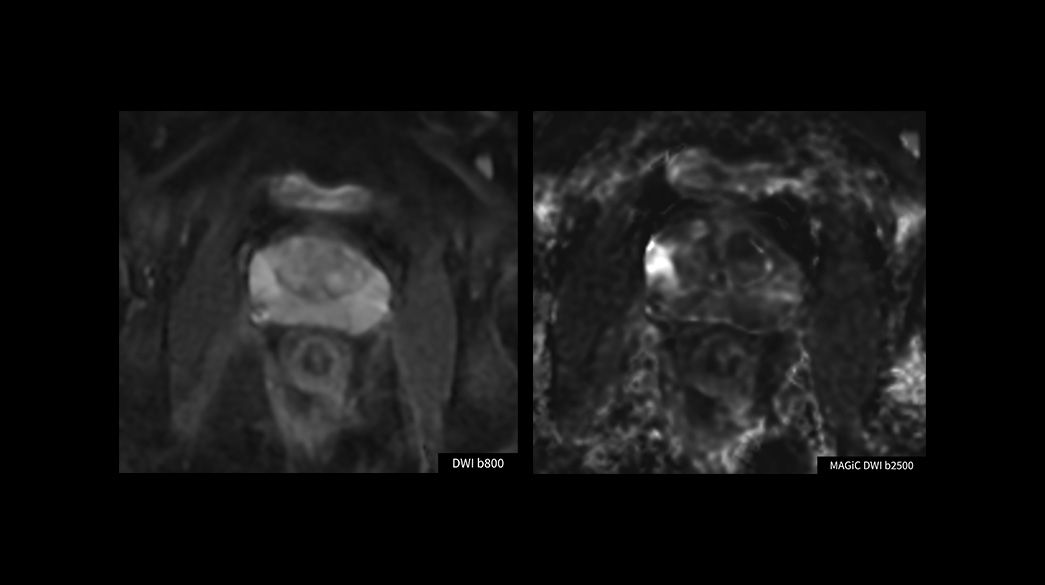

Oncology MR imaging techniques to capture anatomical and morphological data with robust tissue contrast, motion-insensitive and high temporal and spatial resolution for oncological assessment.

Advanced-DWI1040-x-585

Read case study ico-caret-right